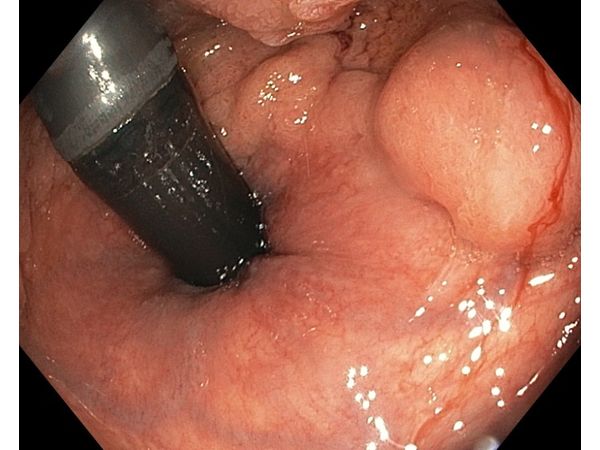

После предоперационной подготовки и очищения толстой кишки пациенту под общим наркозом провели эндоскопическую подслизистую диссекцию: через задний проход с помощью колоноскопа полностью удалили опухоль в пределах здоровых тканей.

Операция в общей сложности длилась 5 часов, из которых 4 часа заняло само удаление. Размер извлечённой опухоли составил 100 × 90 мм.